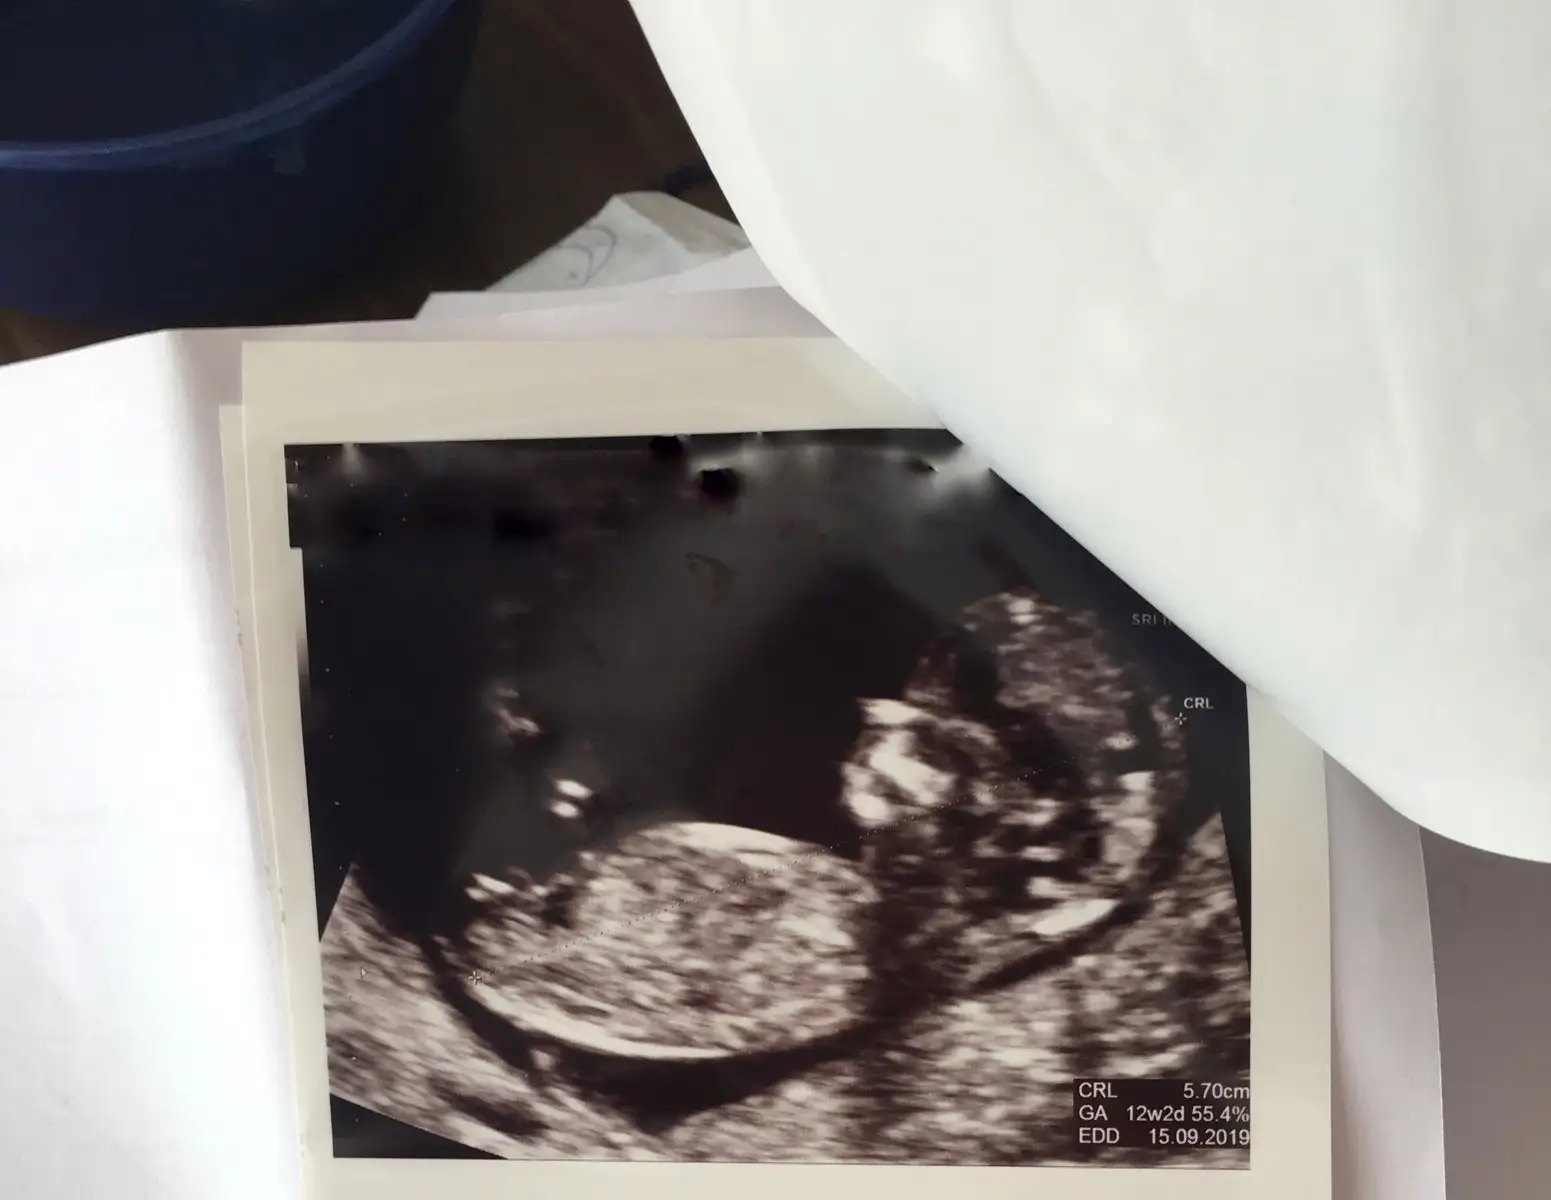

Kesin olmamakla birlikte erkek gibiEki Görüntüle 2242255

Saol canım tesekkür ederim dr da kız dedi bakalım hayırlısı ile sağlıkla gelsin inşallahKesin olmamakla birlikte erkek gibi

İnşallah Canım iki oğlum var ne güzel olur hayırlısı inşallahkız gibi

Kıza benzettim CanımArkadaşlar bana da yorum yapar mısınız lütfen 12 haftalık bebeğim